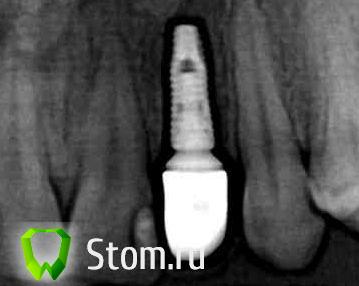

Крупка Опубликовано 20 декабря, 2011 Поделиться Опубликовано 20 декабря, 2011 (изменено) Скажите пожалуйста насколько правильно стоит? Изменено 20 декабря, 2011 пользователем Крупка Ссылка на комментарий

Bier Опубликовано 20 декабря, 2011 Поделиться Опубликовано 20 декабря, 2011 по снимку вроде все ок. Ссылка на комментарий

Крупка Опубликовано 20 декабря, 2011 Автор Поделиться Опубликовано 20 декабря, 2011 панорамный рентген снимок такое выдал, там нету черного такого зазора на самом деле. А как коронка и имплант расположены относительно десны и кости ? Ссылка на комментарий

Крупка Опубликовано 21 декабря, 2011 Автор Поделиться Опубликовано 21 декабря, 2011 коронка разве не сидеть вплотную к импланту, закрывать абатмент и уходить под десну? Ссылка на комментарий

annda Опубликовано 21 декабря, 2011 Поделиться Опубликовано 21 декабря, 2011 Нет,только вплотную к абатменту. Ссылка на комментарий